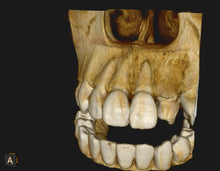

This material is premixed and is ideal for open apices, vital pulp therapy, perforation repair, apical microsurgery and coronal sealing of the root canal system.

- Excellent Radiopacity (10.81)